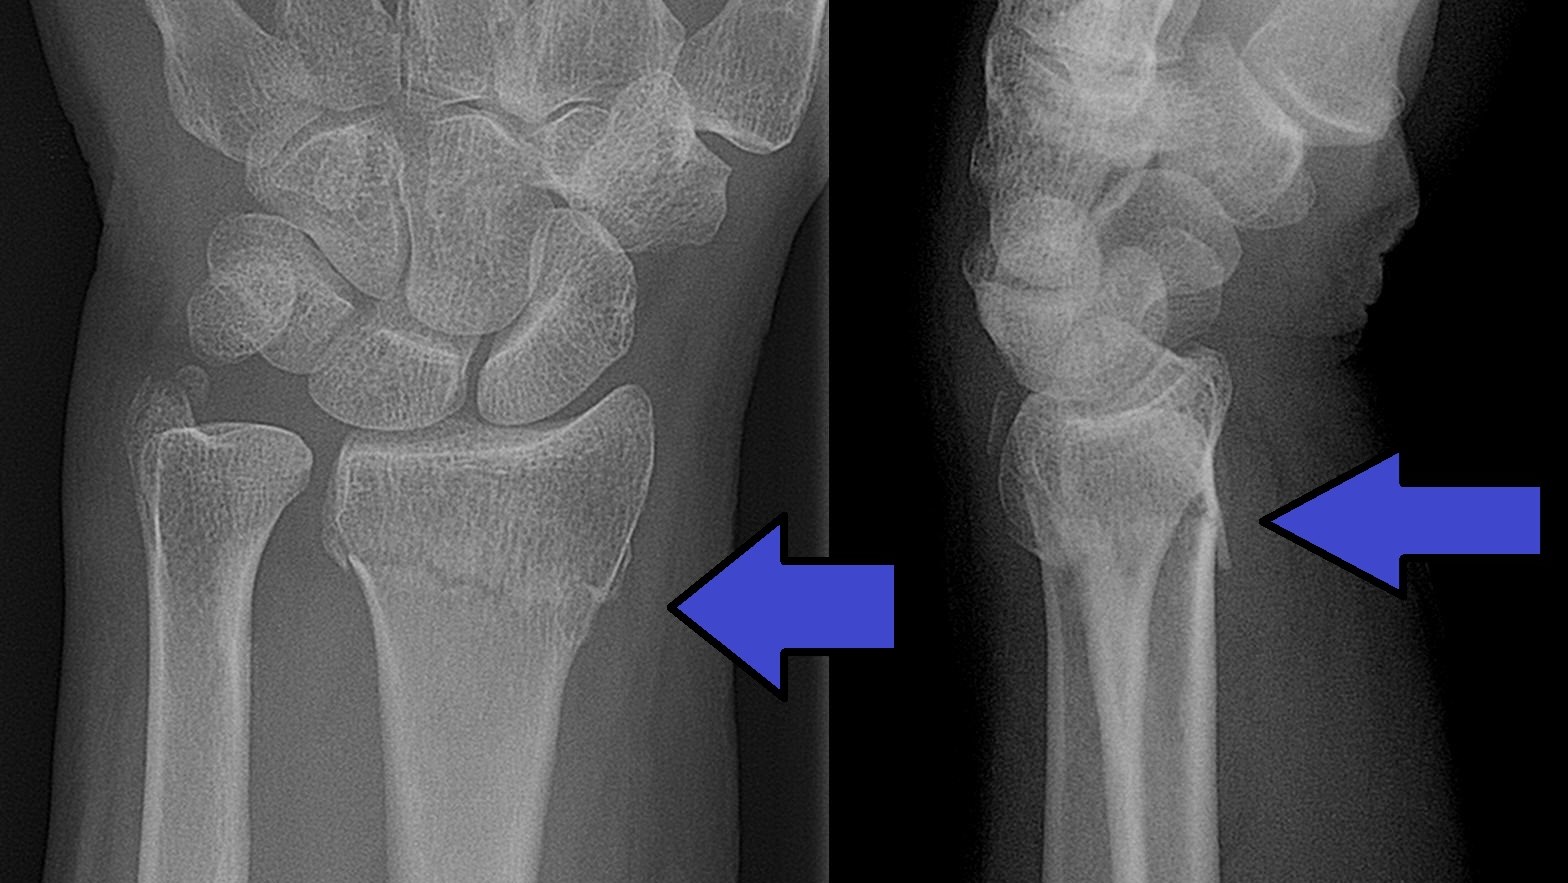

Scaphoideumfraktur

Palpationsömhet i fossa Tabatiére, smärta vid axialt kompression av tummen samt vid dorsalextension respektive radialdeviation av handleden.

Drabbar ofta yngre individer i samband med sportutövning eller efter annat kraftigt dorsalextensionsvåld. Frakturen är ofta svår att identifiera på slätröntgen varför upprepade undersökningar och/eller CT/MR kan behövas.

Vid misstanke om scaphoideumfraktur (adekvat trauma, ömhet i fossa Tabatiére)

- Immobilisera i scaphoideumgips även om röntgen bedöms normal.

- Beställ då röntgenkontroll (utan gips) efter 10-14 dagar! Om röntgen är u a även efter 2 veckor, men status kvarstår: ordna snar MR- eller CT-undersökning!